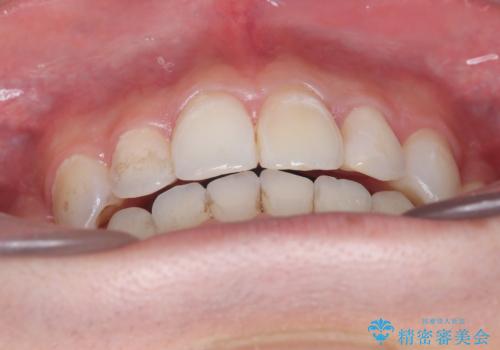

【インビザライン】抜歯矯正で前歯を下げたい。

- 前歯が出ていることを主訴に来院されました。

臼歯関係が上顎前突傾向のため、上顎小臼歯を抜歯してインビザラインにて治療を行いました。

臼歯の咬合を作るために治療終盤ではゴムかけを行なっています。